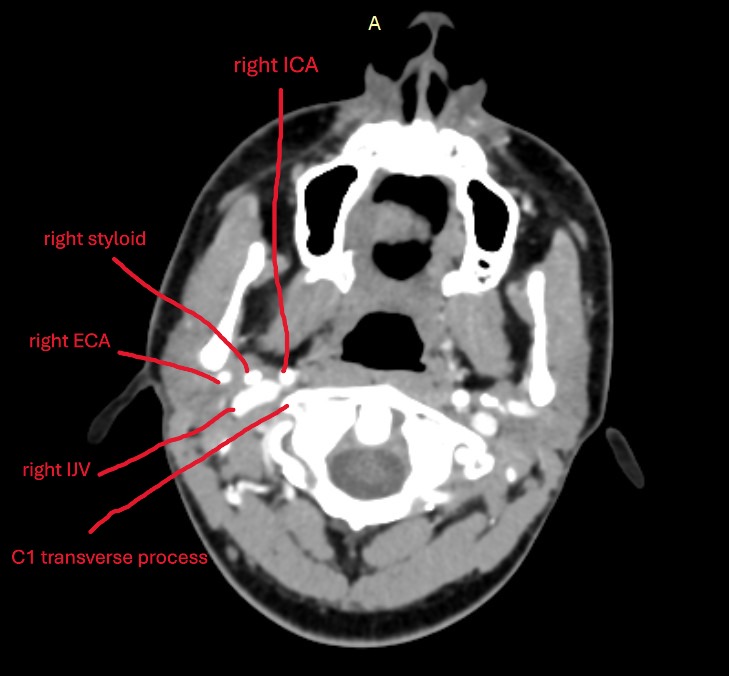

Do you happen to have your original CT scans? If you go into the axial view and screen shot this area (see my attached imaging) of C1, I can see if your IJVs are being compressed!

Your right IJV is getting compressed between your right styloid and C1. This is important not only because of reduced blood flow out of the brain, but also because the vagus nerve runs between the IJV and C1, so if the IJV is compressed than the vagus is compressed and can cause heart rate and blood pressure changes which can cause dizziness. The reduced flow from IJV compression can also cause dizziness and headaches, brainfog things like that.

Your right styloid tip is in contact with your right ECA, which is the artery that supplies your ear with blood, so any pressure changes from your styloid hitting that artery or compressing it, would likely cause pressure changes to your ear which can cause a bunch of ear symptoms (fullness, ringing/tinnitus) and possibly dizziness since the ears are important in the vestibular system.

Not seeing anything at the hyoid. That’s not to say nothing is going on there. I really think your right styloid is the big player here, and it’s possibly effecting your right IJV, right ECA, and right vagus nerve.